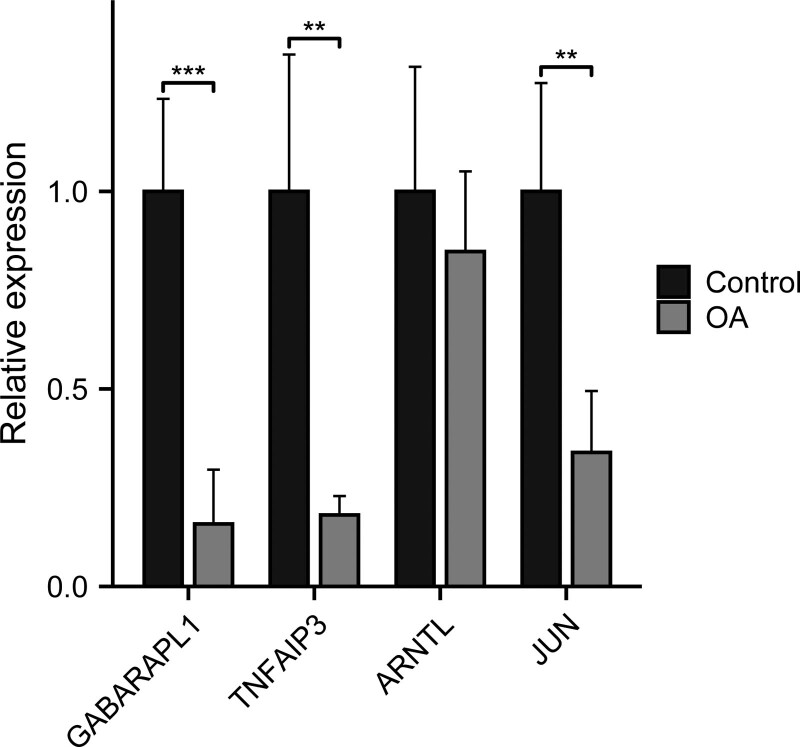

The results showed that the relative expression levels of 4 feature genes including GABARAPL1, TNFAIP3, and JUN were consistent with the results of bioinformatics analysis. ARNTL showed no statistically significant difference (Fig. 7).